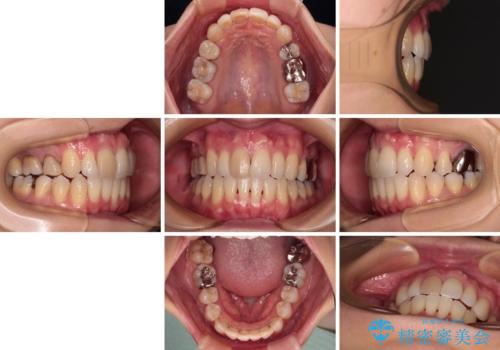

上顎前歯の歯軸が顕著に改善され、非常に口の閉じやすい歯列に仕上げることができました。

上下の咬み合わせは上顎歯列全体が歯1本分前にずれている状態であり、さらに上顎歯列はV字型に尖っていたため、上下前歯は全く接触していない状態でした。

上顎左右第一小臼歯を抜去して、ワイヤー装置にて口元の突出感を改善するよう矯正治療を行うこととしました。